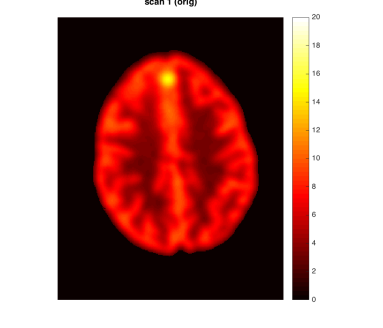

As a motivating example that will be detailed in Section 5, Figure 1 shows data from the phantom experiment in Qin et al., (2017) simulating pre- and post-treatment scans with a tumor lesion. A direct voxelwise difference between the two scans shows a global non-homogeneous background change while failing to detect changes in the lesion (Figure 1, Row 1 and Column 3). This observation suggests that background adjustment is necessary in voxelwise comparisons to reduce confounding by tissue-dependent changes not related to the disease, in order to isolate localized differences that are relevant to assess the disease status.

In the first half of this paper, we study the standardization of a Gaussian mixture model systematically in various but simple ways. We show that, surprisingly, the tail distribution of the standardized scores is favorably close to standard normal in a wide range of scenarios while being conservative at the tails, making it suitable for statistical inference. Compared to the standardization method for background adjustment in Guo et al., (2014) and Qin et al., (2017), we consider several variations using both soft and hard assignment of the observations to latent classes. In the data application in Figure 1, the analysis based on the model-based standardized differences proposed in this paper is successful (Row 2 and Column 3) as the background difference is now randomly distributed around zero and the lesion change is clearly visible; see Section 5 for more details. The distributions of the corresponding standardized scores are evaluated here theoretically, numerically and via simulations. Theoretically, it is shown that the standardized scores are indeed close to standard normal under a variety of extreme parameter settings. In non-extreme parameter settings, it is shown numerically that the soft assignment methods lead to conservative tail probabilities, making them valid for hypothesis testing purposes. It is also shown that the tail probabilities are not very sensitive to the class probabilities, which is an advantage as these are hard to estimate in practice.

In this section, we provide more details about the PET data application discussed in the Introduction (Figure 1). We use the data produced by the lesion change detection study in (Qin et al.,, 2017) using the Hoffman 3-D brain phantom (Hoffman et al.,, 1991), which simulates pre- and post-treatment scans with a tumor lesion. As described there, the brain phantom was filled with FDG radioactive fluid and PET scans were acquired on a GE Discovery ST PET-CT scanner. A malignant lesion was simulated within the central gray matter at a location superior and anterior within the brain, by placing a 1.5 cm diameter sphere of FDG. The tumor-to-background-ratio (TBR) for Scan 1 was 2:1, which was changed to 1.5:1 for Scan 2. Due to the physical construction of the phantom, these two TBR levels were achieved by increasing the activity in the phantom background rather than changing the activity in the lesion (injecting more radio-tracer to the background, while keeping the activity concentration in the lesion constant), effectively producing a reduction in the lesion activity with respect to the background. Image registration was performed between the two scans. The first row of Figure 1 shows one slice of the two scans and their difference (same slice as in Qin et al., (2017)).

By design, there is a large background change but no change in the lesion. A direct difference between the two scans shows a global non-homogeneous background change while failing to detect changes in the lesion (Figure 1, Row 1 and Column 3). In contrast, the analysis based on the model-based standardized differences proposed in this paper is successful (Figure 1, Row 2 and Column 3). Specifically, the second row shows the standardized scores using the proposed robust EM algorithm RB-SGMM and background adjustment via the soft-assignment transformation . The estimated background parameters are those given in (4.1). The standardized scores show a distribution close to standard normal with little anatomical structure except for the lesion. The standardized difference in the third column again has a distribution close to standard normal and exhibits the lesion change clearly at -6 standard deviations away from 0.